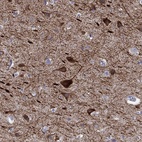

Immunohistochemistry analysis in human cerebral cortex and liver tissues using Anti-KCNH1 antibody. Corresponding KCNH1 RNA-seq data are presented for the same tissues.